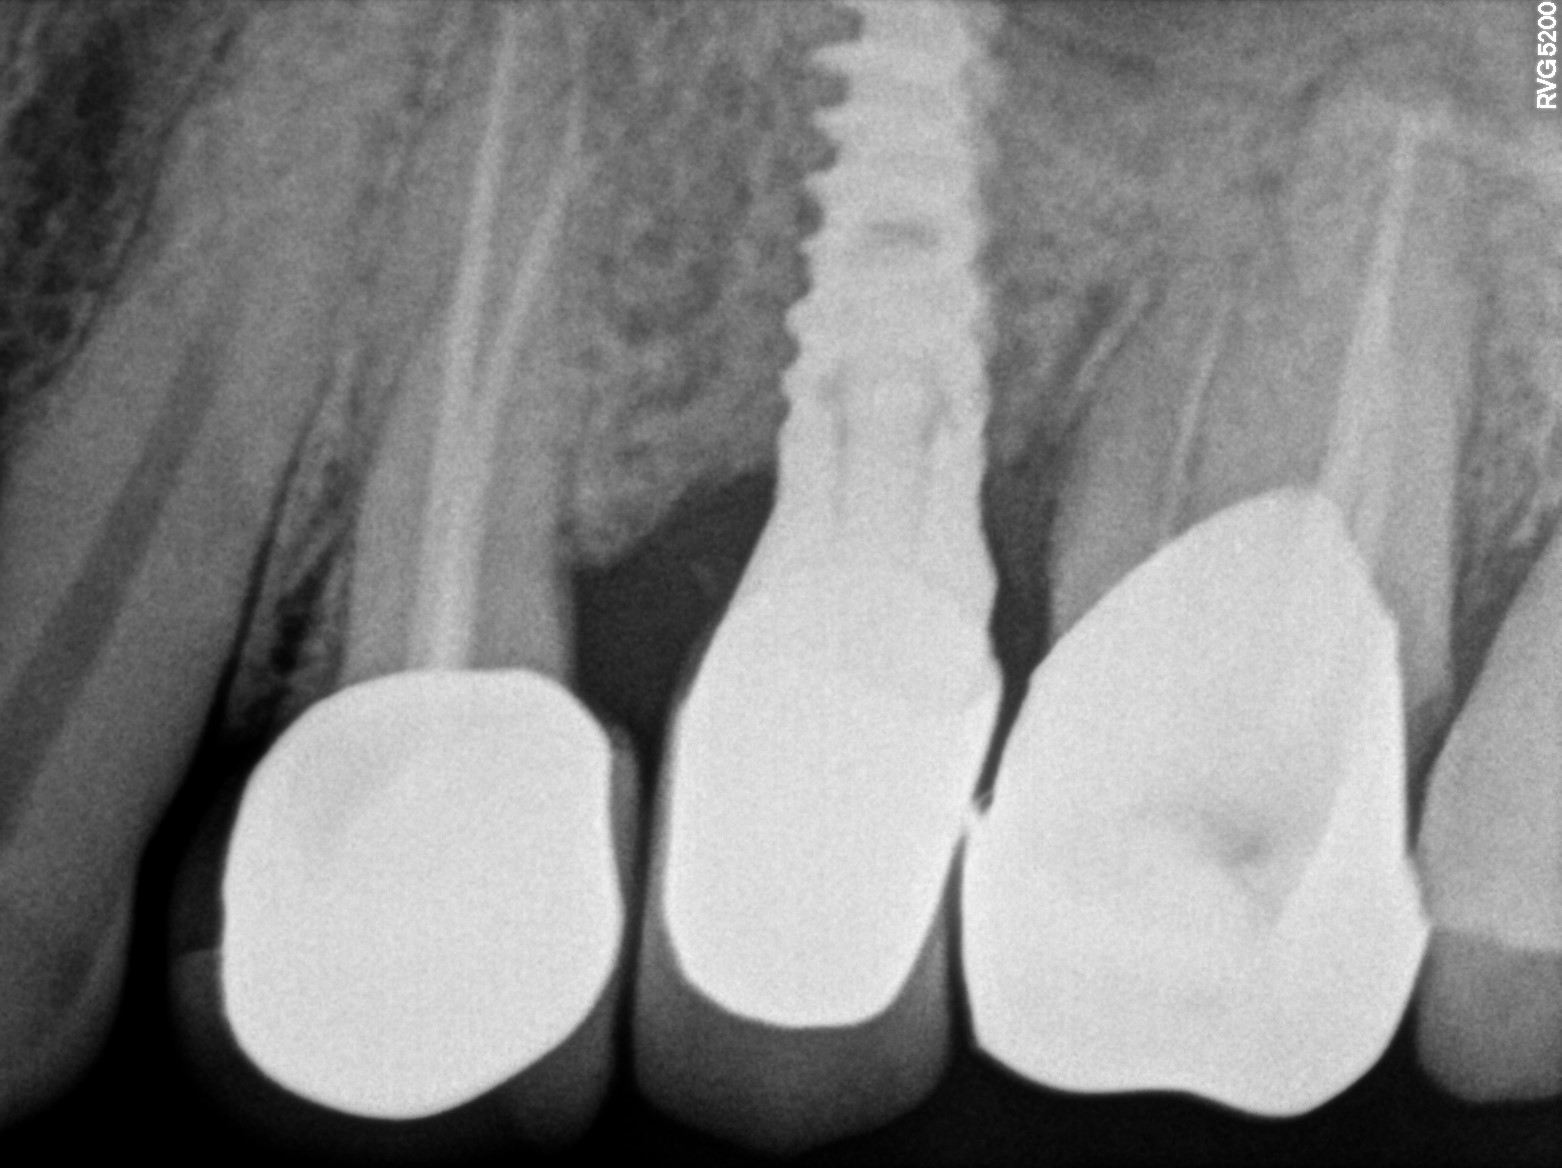

Dental Radiographs FHIR: DocumentReference · LOINC 24641-7

xray_1773475755_1.jpg

24641-7

xray_1773475755_0.jpg